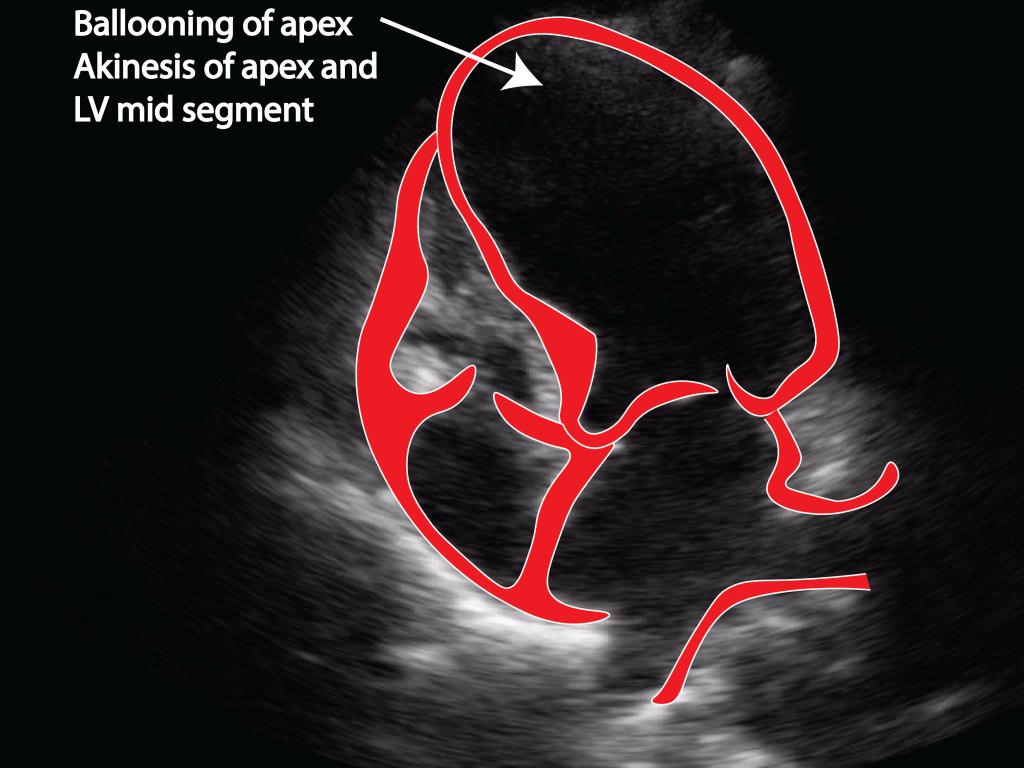

Takotsubo cardiomyopathy Critical Care Sonography Pots Syndrome Cardiomyopathy A cardiomyopathy (e.g., peripartum) could mimic a pots presentation. Pots is said to be a type of dysautonomia characterized by tachycardia brought about by postural shifts in blood volume and circulation. Other testing may be reserved for referral centers. Postural orthostatic tachycardia syndrome (pots) is a chronic and often disabling disorder characterized by orthostatic intolerance with excessive heart rate increase.. Pots Syndrome Cardiomyopathy.